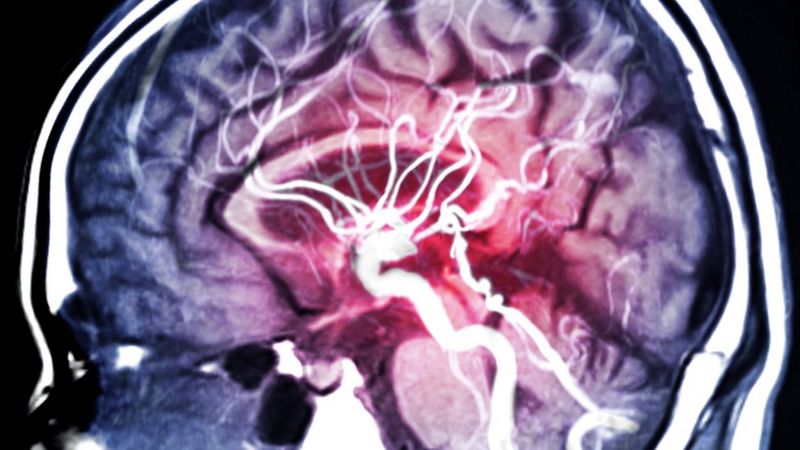

«Hay que imaginarse el sistema de circulación en la cabeza como un árbol que tiene un tronco -una gran arteria- que se divide en ramas cada vez más pequeñas y tan diminutas que ni siquiera tenemos nombres para esos vasos sanguíneos», dice la doctora Koppel.

«El coágulo, que se puede haber formado en el corazón o en las arterias carótidas (arterias principales del cuello), se desplaza por ese sistema que se vuelve cada vez más estrecho, hasta que ya no puede pasar, bloqueando los vasos sanguíneos que alimentan partes del cerebro.

Sin esa irrigación de sangre rica en oxígeno, las células de esa región dejan de funcionar y pueden morir, generando una combinación de síntomas que pueden ir desde debilidad en parte de la cara, dificultades al hablar o caminar, y problemas de visión.